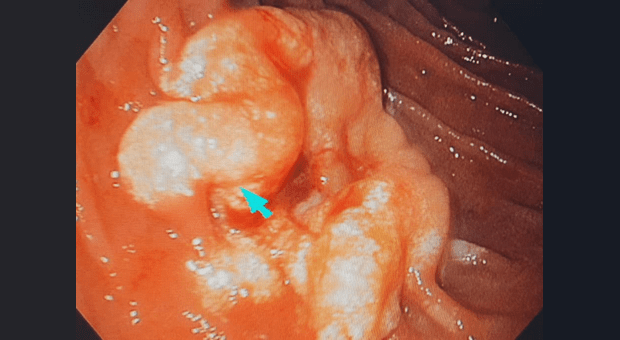

Девушка 1985 года рождения, в анамнезе роды 5 месяцев назад, лактация. ЛХЭ в 2015г. Жалобы на дискомфорт в эпигастрии, вздутие, не температурит. Данное образование в области верхнего дуоденального изгиба, выполнена биопсия, при взятии биопсии, из центра образования, выделилось мутное содержимое в скудном количестве (гной?). Коллеги, ваше мнение. Спасибо.